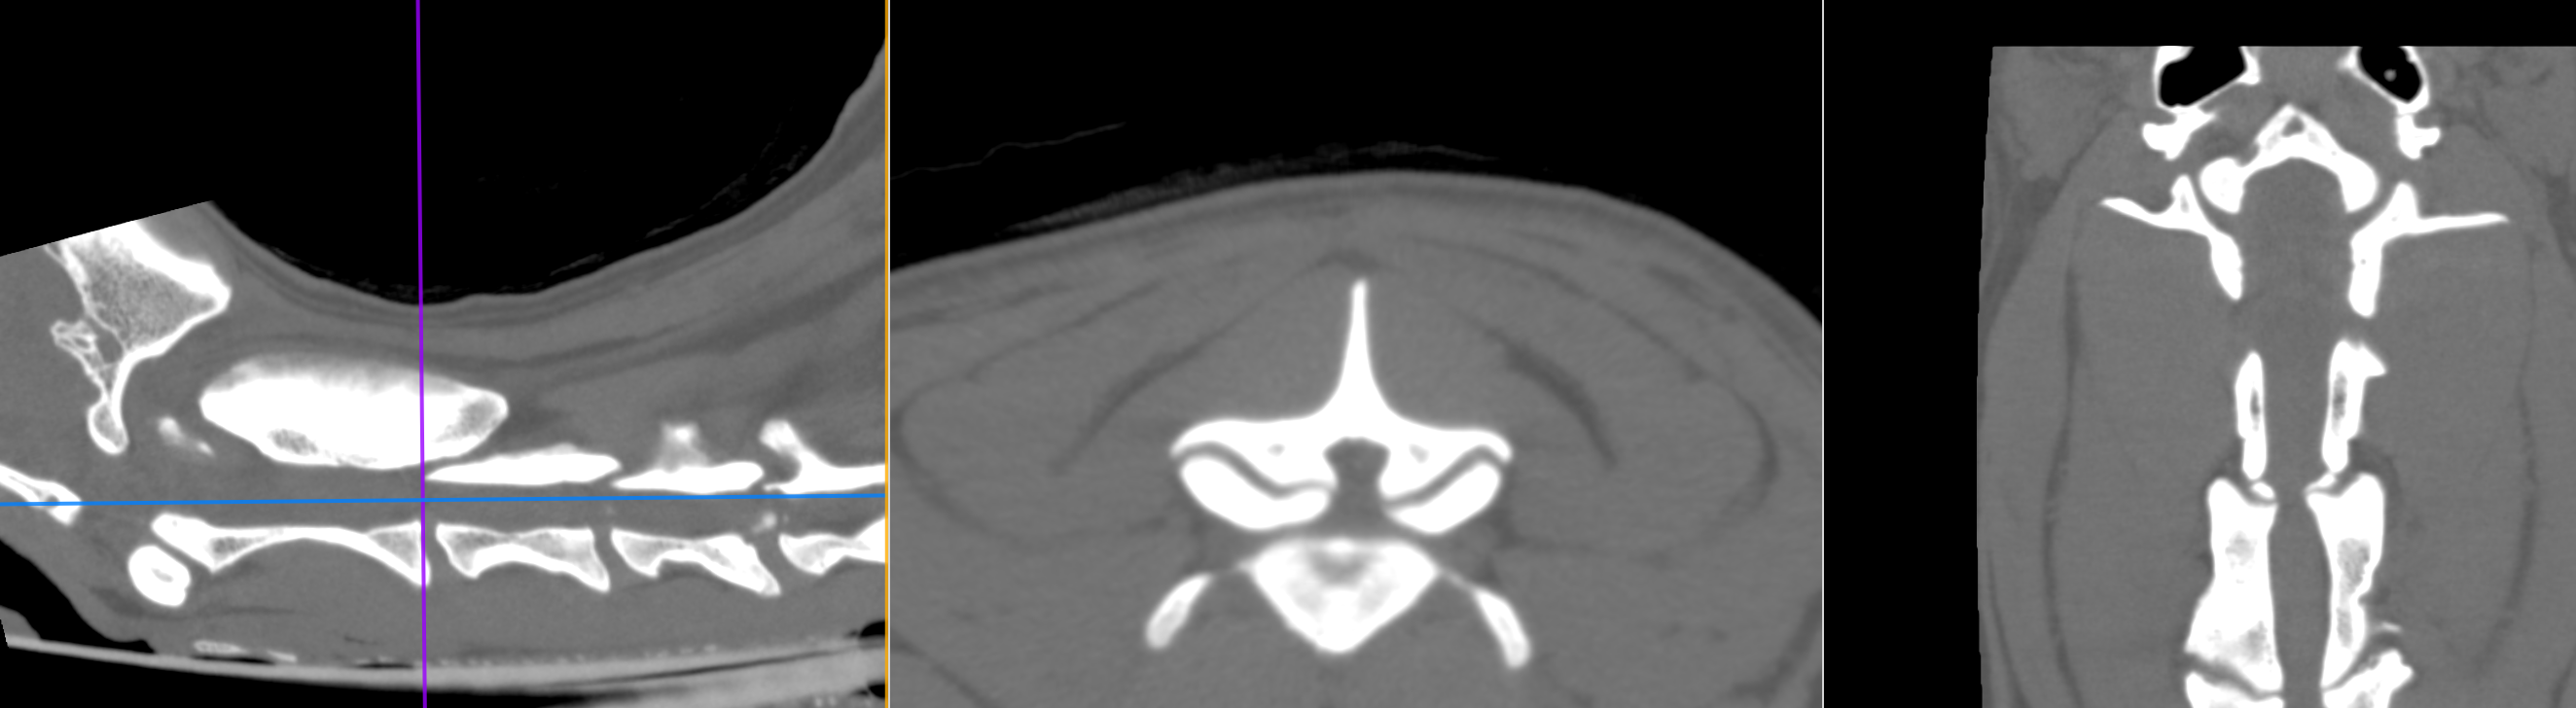

X線CT画像検査です。特に頚椎2−3領域で左右からの重度の圧迫が確認されました。椎間板の問題ではなく、骨自体の形・形態異常からくるものと判断しました。

頚椎の空洞に骨が飛び出ているのがわかります。